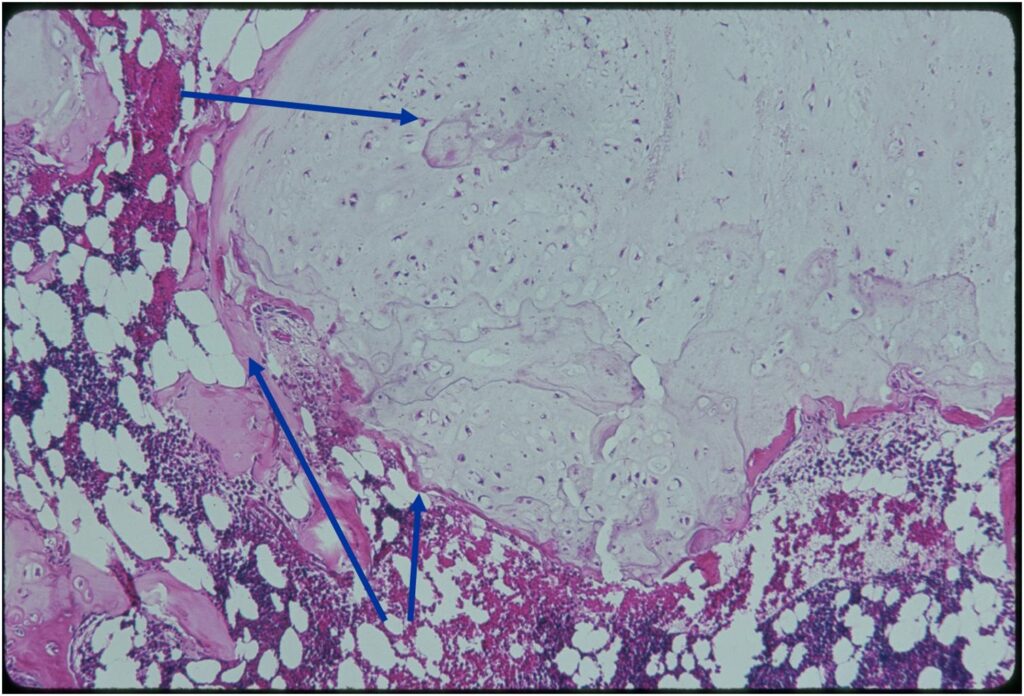

- Enchondromas are well defined lesions with cartilage arranged in lobules that are separated by fibrovascular septa

- Enchondral ossification may occur around periphery of lobules and when calcified appear as “Rings and Arcs” on X-rays

- Cells are in lacunae and have small dark nuclei

- Low cell count, cells appear bland with few chondrocytes and are similar size and shape

- Although some enchondromas may have areas that are hypercellular and may have two or three cells within a lacunae

- No entrapment or destruction of trabeculae

- There should be no myxoid change in long bone lesions (there is occasional myxoid change in enchondromas of the digits)